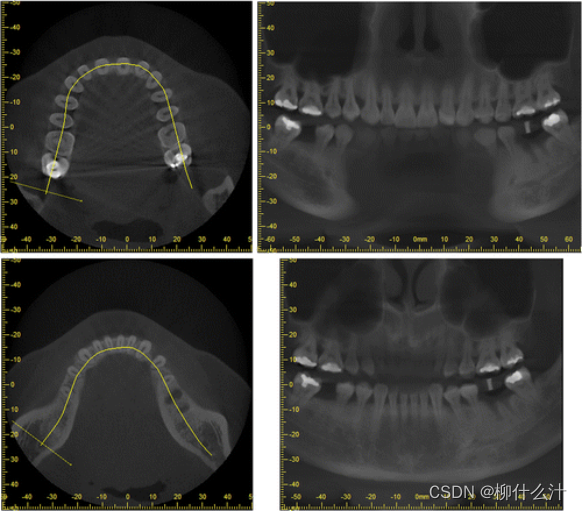

改造可以沿着手动或自动绘制的曲线进行。最常见的是沿牙弓绘制全景曲线,以生成一系列牙齿和骨骼的合成全景图(图00和01)。由于这些合成全景图像的厚度较小,通常不可能在一张图像中看到上下牙弓的情况。因此,通常需要为上、下牙弓分别绘制曲线(图02)。另外,可以计算出这些合成全景图的射线和,类似于从全景X光片上获得的图像。图23显示了不同厚度的合成全景堆叠的射线和全景图像。

沿着用户在轴向平面(左)绘制的曲线合成的全景图像(右)。

沿着与图20所示的曲线略微靠前或靠后的地方,额外的合成全景图像。

上颚(顶部)和下颚(底部)的合成全景图像。

左图:横断面图像的位置,垂直于全景曲线,显示在一个轴向切片上。右图:沿曲线不同位置的横断面图像。